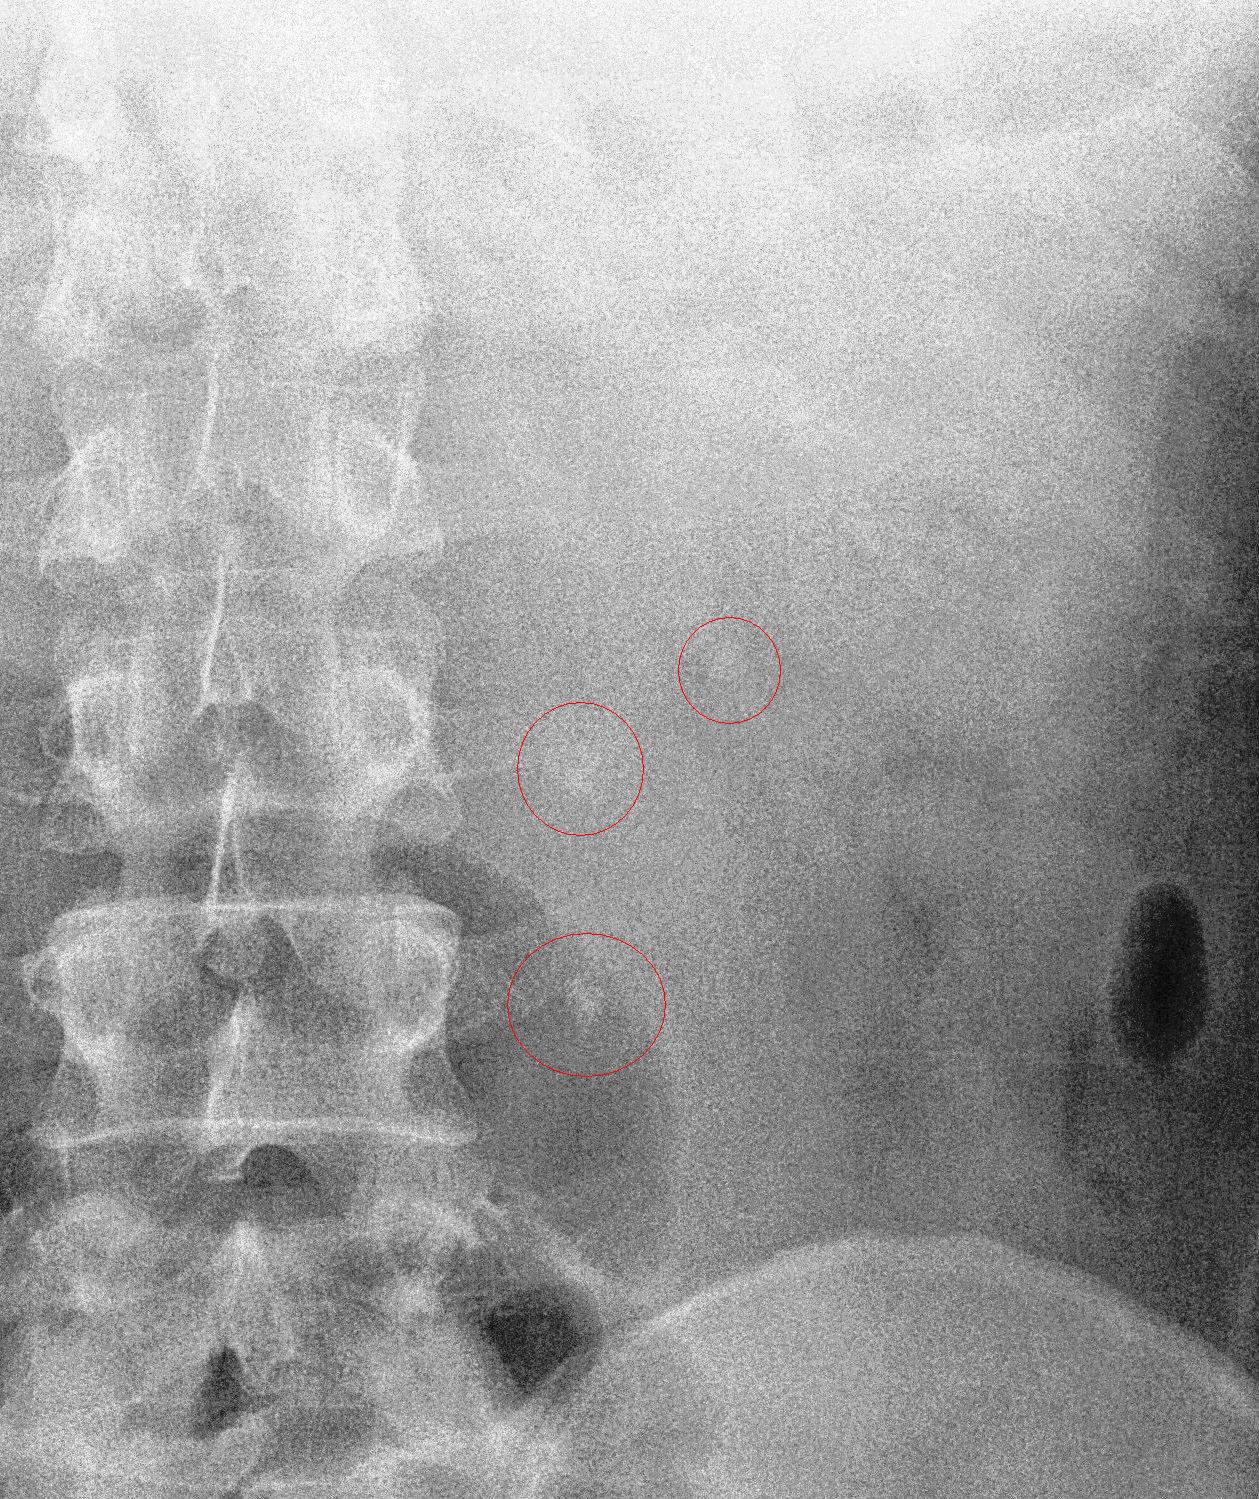

But the Urine FEME came back positive for RBCs, so my provisional diagnosis shifted towards urolithiasis. I downloaded the X-ray film and e-mailed it to a surgeon in Hospital Kuala Lumpur. He confirmed my suspicions by replying, “Congratulations, you got triplets!”.

So two days later, I arranged for an ultrasound appointment to confirm the diagnosis of urolithiasis.

The ultrasound report confirmed the diagnosis. I started treating myself by ingesting potassium citrate mixture 3 times a day to alkalinise my urine. I also had UFEME done regularly to monitor the presence of RBCs in the urine. A week later on 17th Feb, when the RBCs were no longer being detected in the urine, I had another KUB X-ray done.

The KUB on the 17th indicated that the bottom stone was still at the same site but the other two stones has come together and now were on top of each other. But there was no RBCs coming through, so either the bottom stone was blocking everything or the bottom stone had stabilised and was no longer cutting across the surface of my ureter, so no blood in the urine.